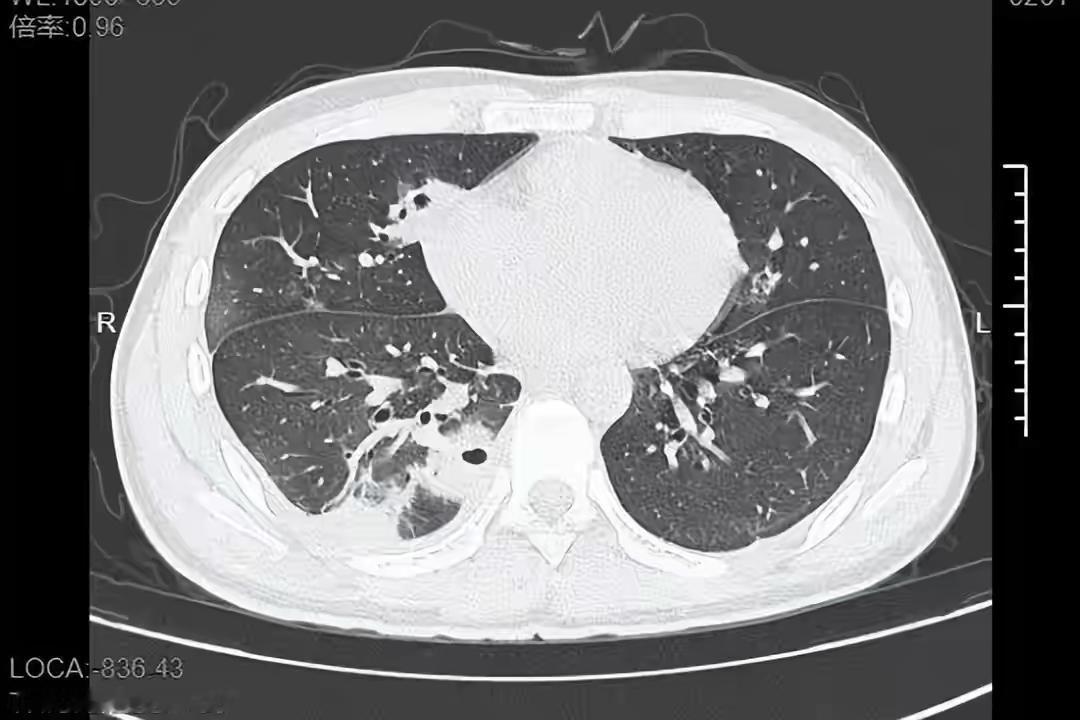

真的惊到我了!一个20岁的小伙子,就因为挤了颗脸上的痘痘,直接把自己送进医院,肺里硬生生被细菌“啃”出十几个空洞,想想都后怕! 很多人觉得挤痘痘是小事,尤其是脸上冒痘总忍不住上手,但你们不知道,脸部“危险三角区”的痘痘就是颗“定时炸弹”。没洗手就挤,细菌很容易顺着血管钻进身体,轻则引发感染,重则像这个男生一样诱发败血症,甚至危及生命。 这根本不是“运气差”,而是我们对健康的轻视!别觉得年轻就可以肆意挥霍身体,那些看似不起眼的小习惯,可能藏着致命的风险。保护自己从来不是大题小做,而是从拒绝手欠挤痘痘这种小事开始。 你以前是不是也总忍不住挤痘痘?现在知道危害后还会乱来了吗?评论区说说你的看法~